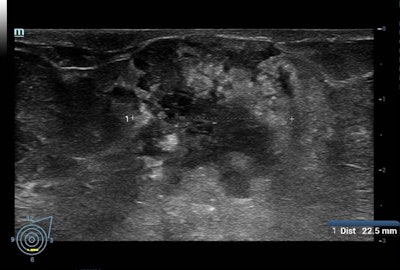

The strength of the national screening program lies in the fact that it is decentralized, meaning it can take place locally -- in any of the 2,700 centers across France that provide mammography -- and can be tailored to the patient, according to Ceugnart, who is head of imaging at the Oscar Lambret Centre in Lille. Ultrasound is offered systematically to patients with dense breasts, and it is performed at the same screening consultation by a radiologist, rather than in a follow-up appointment.

For example, the Adjunct Screening With Tomosynthesis or Ultrasound in Women With Mammography-Negative Dense Breasts (ASTOUND) study showed that ultrasound has better incremental breast cancer detection than DBT in mammography-negative dense breasts at a similar false-positive recall rate. However, DBT detected more than 50% of the additional breast cancers in these women, according to the authors.

Meanwhile, the Japan Strategic Anticancer Randomized Trial (J-START) revealed that adjunct ultrasound increased sensitivity and the detection rate of early-stage cancers.